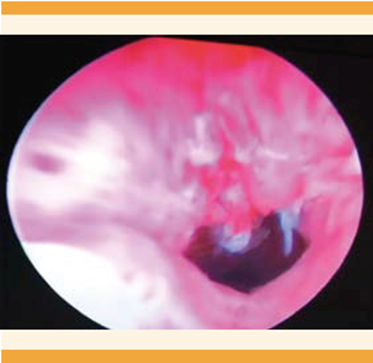

Acudió a la consulta externa de Ginecología debido a un dolor pélvico 7-10 en la escala visual análoga del dolor (EVA), con sangrados menstruales regulares aumentados en volumen y dos intentos fallidos de extracción del DIU en un consultorio. En la exploración física el abdomen se palpó blando, depresible, doloroso a la palpación profunda, el útero no delimitado, sin masas palpables. En la especuloscopia no se observaron los hilos del DIU, sin huellas de sangrado. El estado hemodinámico de la paciente era estable, sin datos de irritación peritoneal. La radiografía abdominopélvica anteroposterior evidenció el DIU en el hueco pélvico izquierdo (Figura 1). El ultrasonido endovaginal el útero se observó en retroflexión de 68 x 37 x 47 mm. El endometrio trilaminar, los anexos derechos normales, al igual que el ovario izquierdo. El fondo de saco sin datos de líquido libre (Figura 2). Para precisar la ubicación del dispositivo se practicó la histeroscopia de consultorio en la que se visualizó el área de granulación en la cara anterior derecha, probable falsa vía. Se corroboró la ausencia del DIU en la cavidad (Figura 3). La TAC simple y contrastada reportó al útero inclinado hacia la izquierda, con el dispositivo intrauterino en la trompa uterina izquierda. Figura 4

Figura 3 Histeroscopia: se observa el área de granulación en la cara anterior derecha, probable falsa vía.